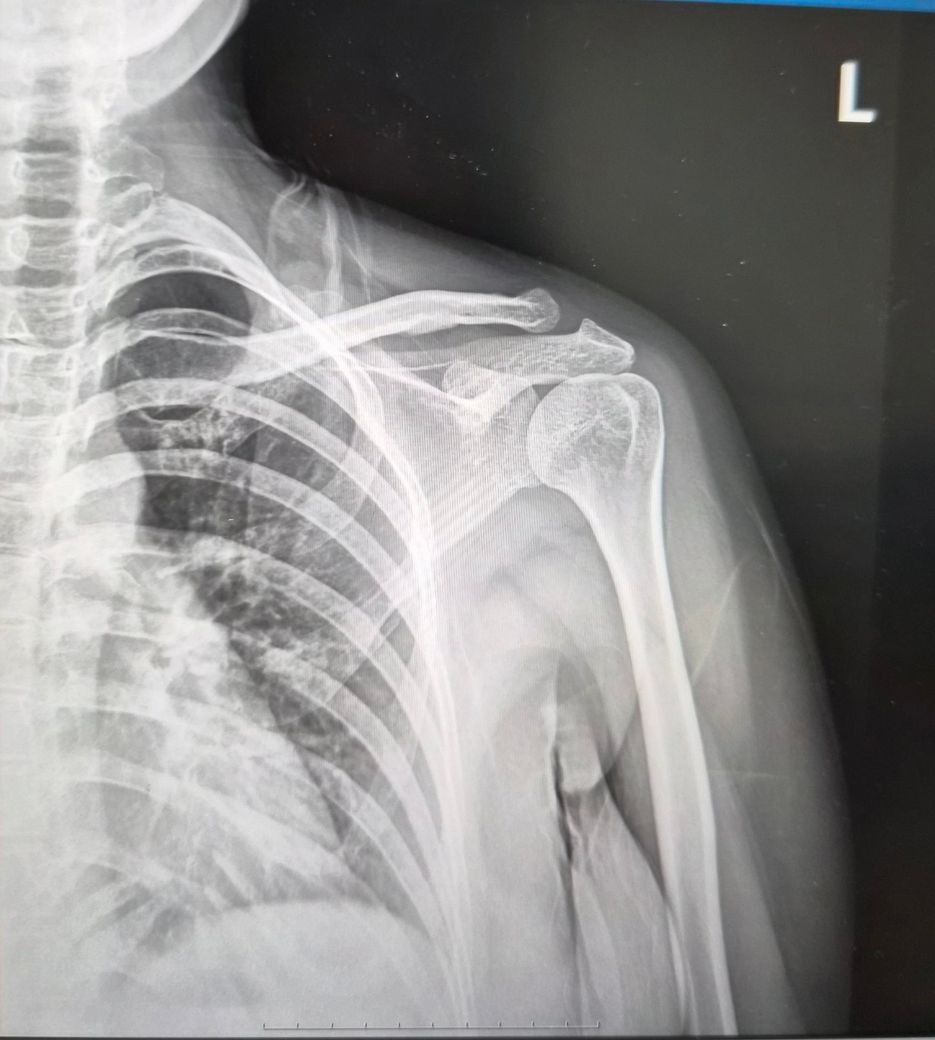

왼쪽어께 통증있어요.앗까는 엑스레이 사진만 올렸었는데 이번에는 MRI같이 올려봐요.

엑스레이사진은 왼쪽어께사진인데 1번 사진은

2025년10월14일사진이구요

2번사진은 2026년2월19일 사진입니다.

두 엑스레이 상에서도 다른점이 있나요?

견봉이랑 팔뼈 더 좁아지지는 않았나요?

두 X-ray를 비교하면 "견봉–상완골 간격이 아주 약간 더 답답해 보일 수는 있으나" 급격히 좁아진 소견은 뚜렷하진 않습니다.

엑스레이 두장의 사진만으론 판단을 하긴 어렵지만 확연히 공간이 좁아보이지만 이 부분이 엑스레이 촬영시 통증에 의한 보상작용으로 자세적인 문제로 인해 공간이 좁아보일수도 있기에 단정을 짓긴 어렵습니다.